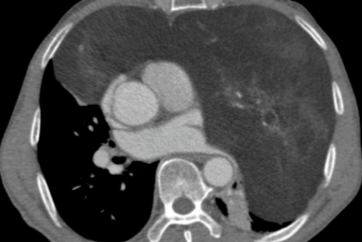

妙手「拆弹」解重负 七旬老人获新生

2026-04-02 -